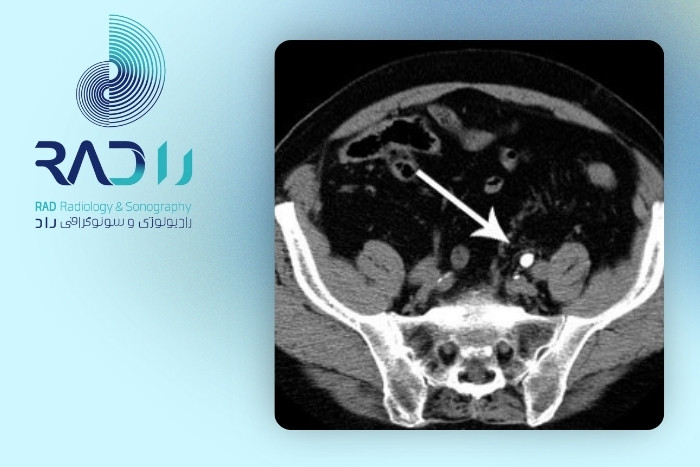

تشخیص سنگ کلیه با سونوگرافی یا سیتیاسکن

مواردی که دقت مطلق لازم داریم یا موارد مشکوک که سونوگرافی جواب نداده: سیتیاسکن بدون تزریق بهترین گزینه است.

در مجموع اگر بخواهیم با ایمنی بالا و بدون اشعه بررسی کنیم سونوگرافی روش اول است. اگر به دنبال تشخیص دقیق در هر اندازه و هر محل از سنگ باشیم سیتیاسکن انتخاب نهایی است. برای انجام سونوگرافی در بلوار کشاورز میتوانید به مرکز تصویربرداری راد مراجعه کنید.